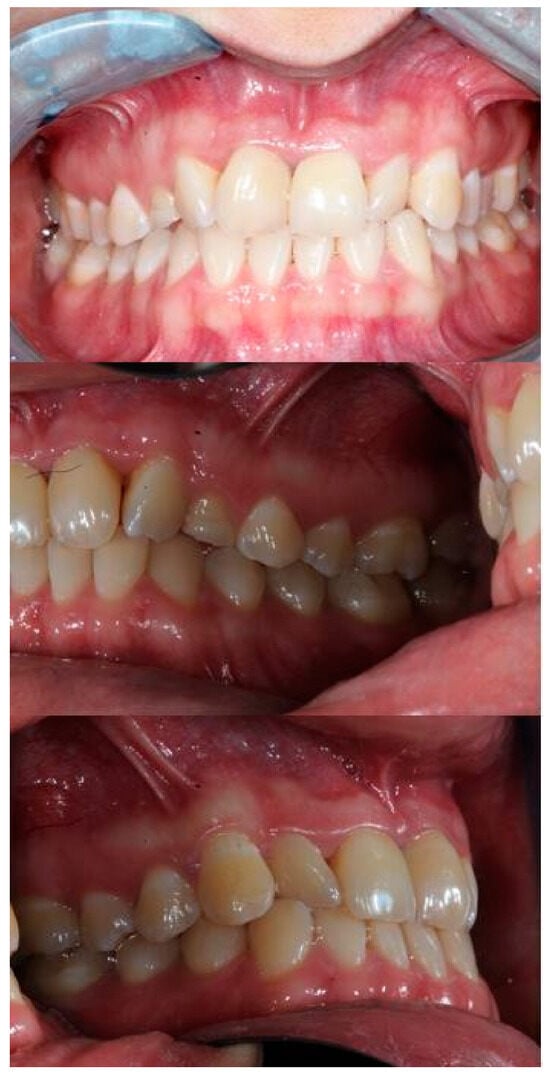

2. Case Report